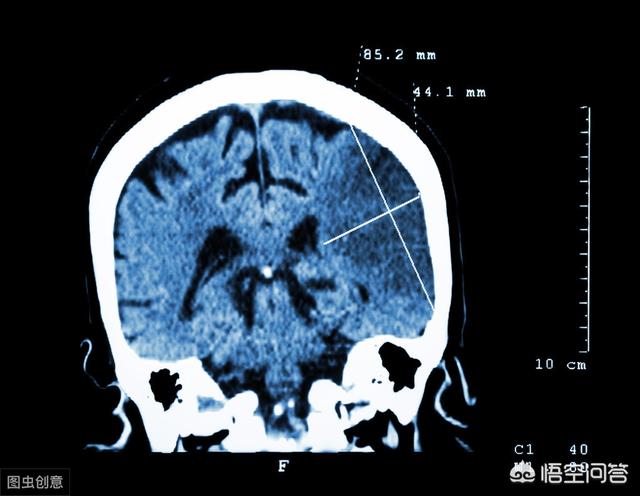

À son arrivée à l'hôpital, le médecin a vérifié les signes et mesuré la tension artérielle, puis a effectué un scanner du cerveau par le canal vert, qui a révélé une grave obstruction des vaisseaux sanguins du cerveau, qui mettrait en danger la vie du patient s'il n'était pas réanimé à temps !

Les résultats d'un scanner cérébral ont révélé une grave obstruction des vaisseaux sanguins cérébraux, ce qui pourrait mettre la vie en danger à tout moment.

Les membres de la famille ont vu, immédiatement composé le 120, le médecin est arrivé, une compréhension générale de la situation, à l'hôpital immédiatement effectué un examen du cerveau ct, les résultats montrent que le blocage du cerveau est grave, immédiatement effectué la thérapie thrombolytique, parce que l'état est plus grave, pas la première crise d'infarctus cérébral, donc cette fois, donner en vertu de la maladie critique.